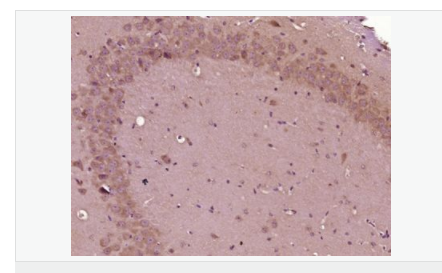

| 產(chǎn)品應(yīng)用 | WB=1:500-2000 IHC-P=1:100-500 IHC-F=1:100-500 ICC=1:100-500 IF=1:100-500 (石蠟切片需做抗原修復(fù)) not yet tested in other applications. optimal dilutions/concentrations should be determined by the end user. |

| 產(chǎn)品介紹 | This gene encodes the epsilon member of the sarcoglycan family. Sarcoglycans are transmembrane proteins that are components of the dystrophin-glycoprotein complex, which link the actin cytoskeleton to the extracellular matrix. Unlike other family members which are predominantly expressed in striated muscle, the epsilon sarcoglycan is more broadly expressed. Mutations in this gene are associated with myoclonus-dystonia syndrome. This gene is imprinted, with preferential expression from the paternal allele. Alternatively spliced transcript variants encoding different isoforms have been found for this gene.[provided by RefSeq, Oct 2010] Function: Component of the sarcoglycan complex, a subcomplex of the dystrophin-glycoprotein complex which forms a link between the F-actin cytoskeleton and the extracellular matrix. Subcellular Location: Cell membrane > sarcolemma. Cytoplasm > cytoskeleton. Tissue Specificity: Ubiquitous. DISEASE: Defects in SGCE are a cause of dystonia type 11 (DYT11) [MIM:159900]; also known as myoclonic dystonia or alcohol-responsive dystonia. DYT11 is a myoclonic dystonia. Dystonia is defined by the presence of sustained involuntary muscle contractions, often leading to abnormal postures. DYT11 is characterized by involuntary lightning jerks and dystonic movements and postures alleviated by alcohol. Inheritance is autosomal dominant. The age of onset, pattern of body involvement, presence of myoclonus and response to alcohol are all variable. Similarity: Belongs to the sarcoglycan alpha/epsilon family. SWISS: O43556 Gene ID: 8910 Database links: Entrez Gene: 8910 Human Entrez Gene: 20392 Mouse Omim: 604149 Human SwissProt: O43556 Human SwissProt: O70258 Mouse Unigene: 371199 Human Unigene: 8739 Mouse Unigene: 185815 Rat Important Note: This product as supplied is intended for research use only, not for use in human, therapeutic or diagnostic applications. |